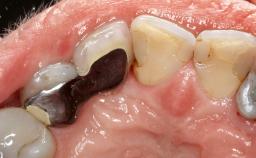

A 63-year-old male patient was referred to the post-graduate periodontal clinic of the Complutense University of Madrid for the treatment of peri-implantitis. According to the patient’s record, all his maxillary teeth had been extracted ten years previously due to severe periodontitis, and a full-mouth implant-supported restoration on eight implants was placed. No supportive periodontal therapy was provided apart from occasional check-ups by the restorative dentist.